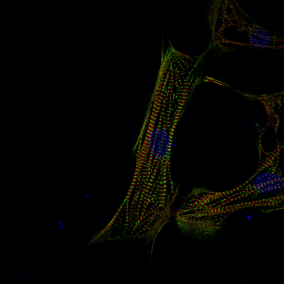

Mit modernen Methoden der Einzelzellsequenzierung, die sie zuvor an die Besonderheiten des Herzgewebes angepasst hatten, mit maschinellem Lernen und Bildgebungsverfahren haben die Wissenschaftler*innen herausgefunden, dass sich die Zellen in diesen Regionen stark voneinander unterscheiden. In jeder Region gab es ein spezifisches Set von Zellen, was Unterschiede in der Entwicklung unterstreicht und möglicherweiser zu unterschiedlichen Reaktionen auf eine Behandlung führt.